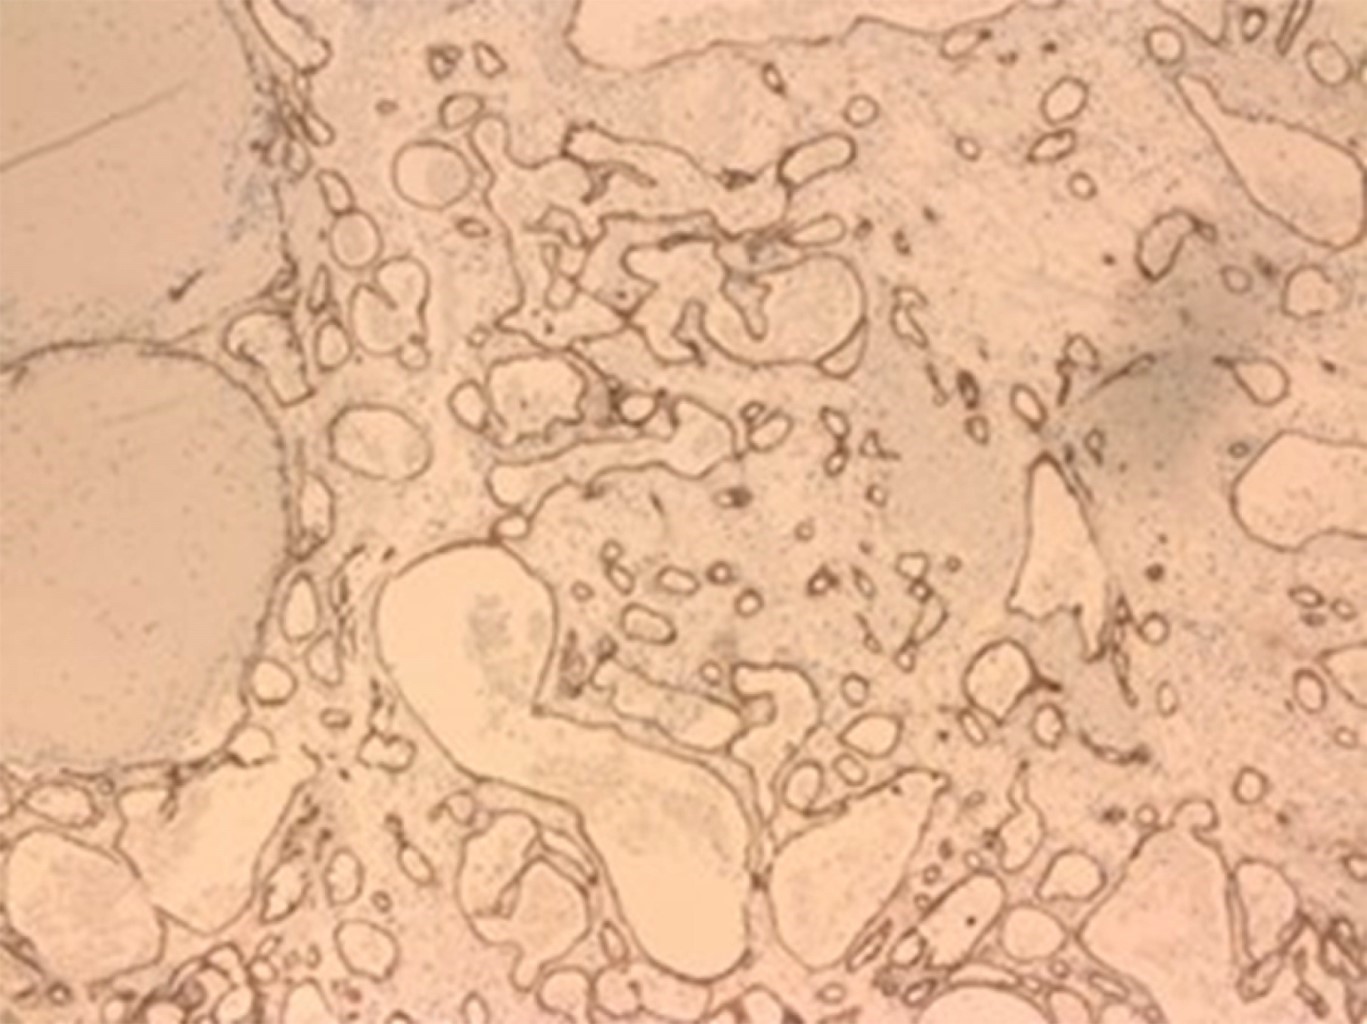

Se realiza biopsia incisional de lesión adyacente al diente 4.8 y unas semanas más tarde se confirma el diagnóstico histopatológico de granuloma piogénico (Figuras 1, 2 y 3). En ese momento se planifica exodoncia de los dientes 1.8, 3.8 y 4.8, junto con la exéresis completa de la lesión bajo anestesia general.

Figura 1

Figura 2